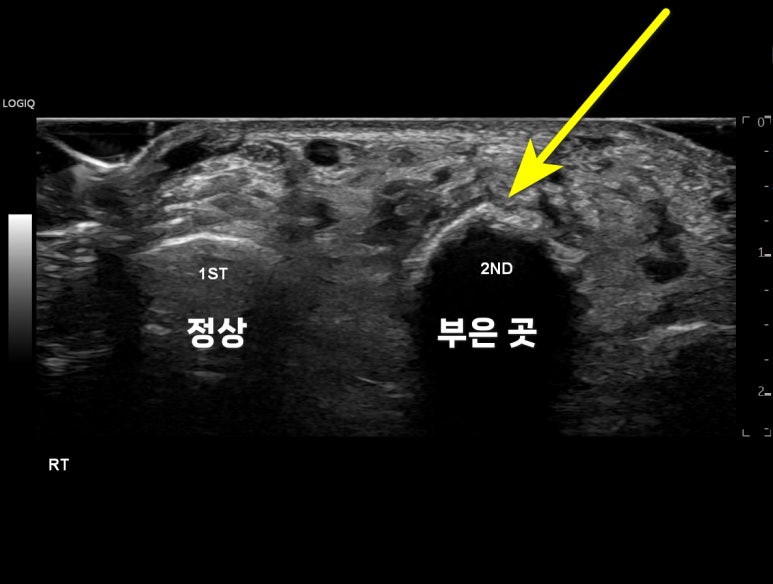

프로브를 돌려

엄지발가락과 비교해봅니다.

엄지 발가락은

곡선으로 깨끗한데,

두번째 발가락은

울퉁불퉁한 가골이 의심됩니다.

여기서 끝이 아닙니다

뼈가 어긋나는

이거나

어긋나지 않더라도

근위 발가락(Proximal phalanx) 관절선을

침범하는 경우

수술이 필요할 수 있거든요.